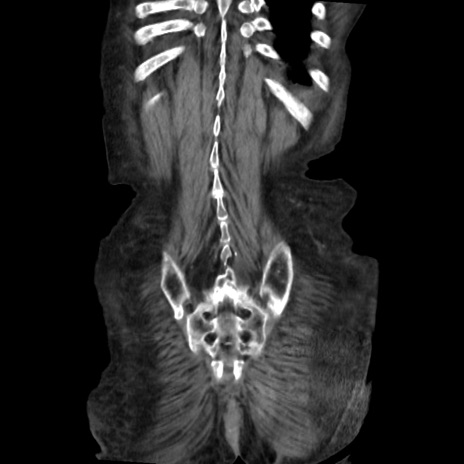

矢状断像